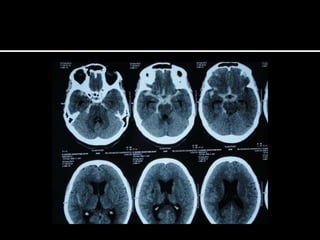

   Sub acute and progressive headache

   New onset >40 yrs of age

   Change in pattern(intensity of pain, frequency of

attacks, new features, decreased response to treatment)

   Association : nausea or vomiting not explained by migraine

or systemic illness ; nocturnal occurrence or morning

awakening; precipitation or worsening by changes in posture

or Valsalva maneuver; confusion, seizures, weakness

   Abnormalities on neuro.examination